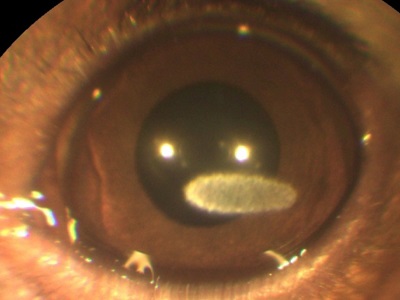

Opacifierea cristalinului (cataractă) este adesea interpretată ca un „spin“. Se sigilează nucleul de lentile, de asemenea, pare tulbure.

Cataracta poate avea loc din motive genetice (cea mai comună cauză), ca urmare a diabetului zaharat, penetrante leziuni corneene, radiații ionizante, și așa mai departe. În funcție de gradul de maturitate a algoritmului de acțiune a cataractei selectat. Cel mai eficient mod de a trata cataracta - o intervenție chirurgicală. Distrugerea substanței opace transportate, eliminarea ei și implantarea lentilelor speciale.

Pentru a distinge cataractă și etanșează miezul necesar să se efectueze examinarea ochilor: biomicroscopie, oftalmoscopie, etc. Pentru a face acest lucru, prezența echipamentului oftalmic este necesar.!